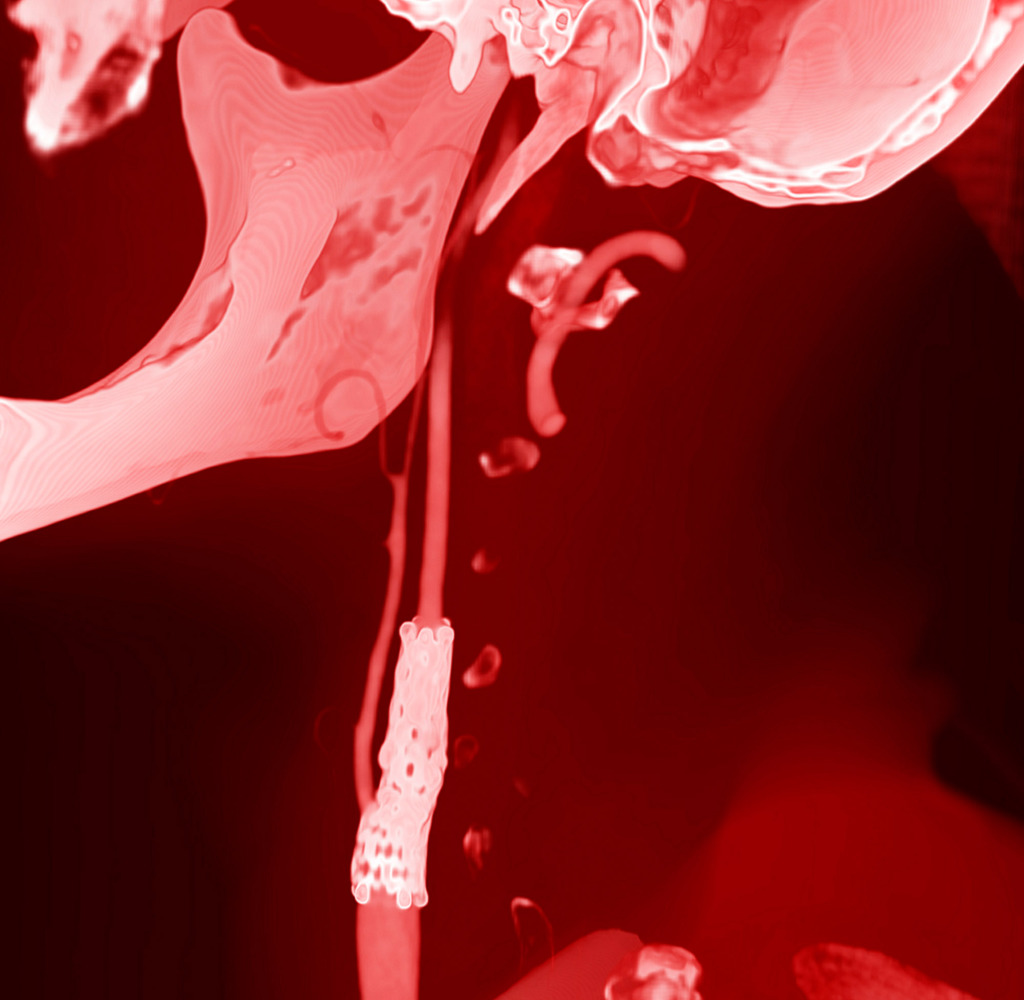

At a lecture on radiology I saw a simple 3D visualisation of a CT examination for the first time. It made an impression on me and the same day at home I started looking for information and software for independent processing of DICOM images. After a few hours, I managed to get a three-dimensional image.

The program for processing radiological images (DICOM archives) allows you to create and look at a three-dimensional image from different angles.

If you change the location of the virtual lens, thereby changing the perspective, you can get such images.

I simply create a table where the radiological density of the material can correspond to any colour.

After combining different shades, I only have to choose what I like the most.